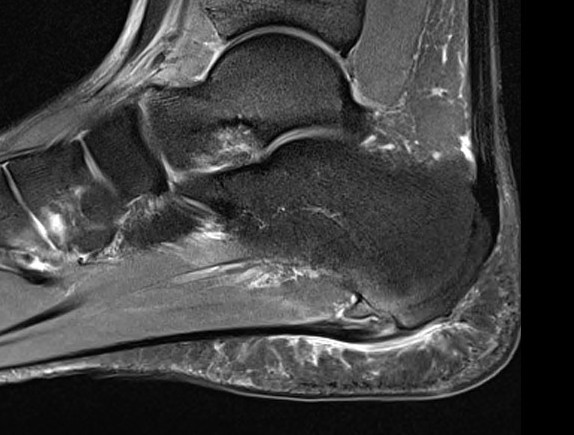

MRI

Thickened plantar fascia with tears

Exclude - retrocalcaneal bursitis / calcaneal stress fracture / Baxter's neuroma / tarsal tunnel syndrome